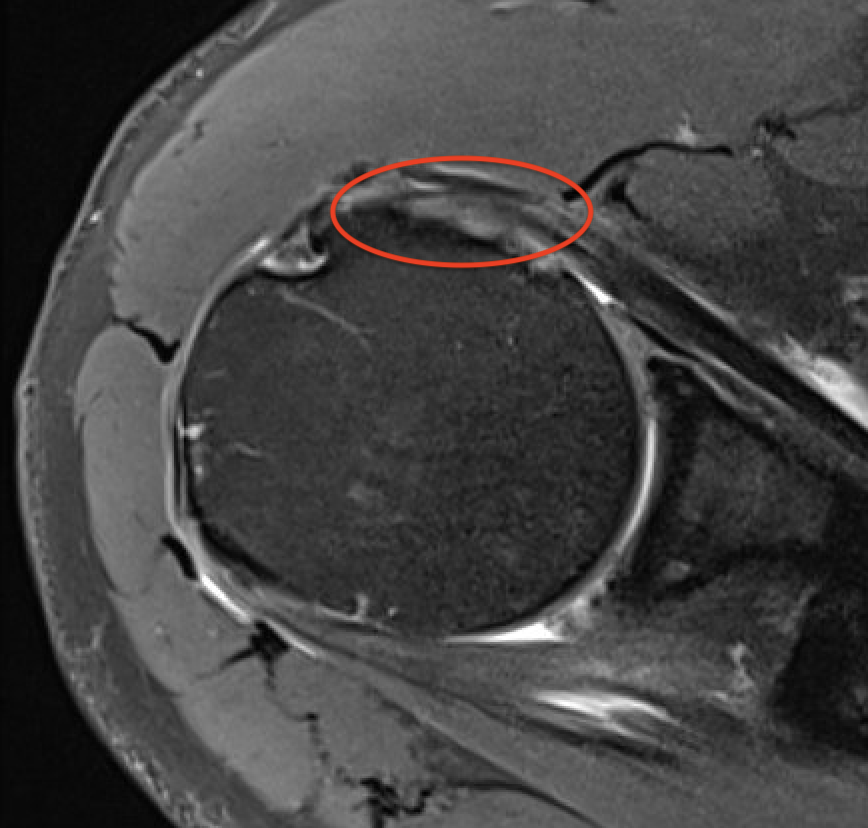

MRI

Patterns

- full thickness minimally retracted tears

Full thickness minimally retracted subscapularis tear